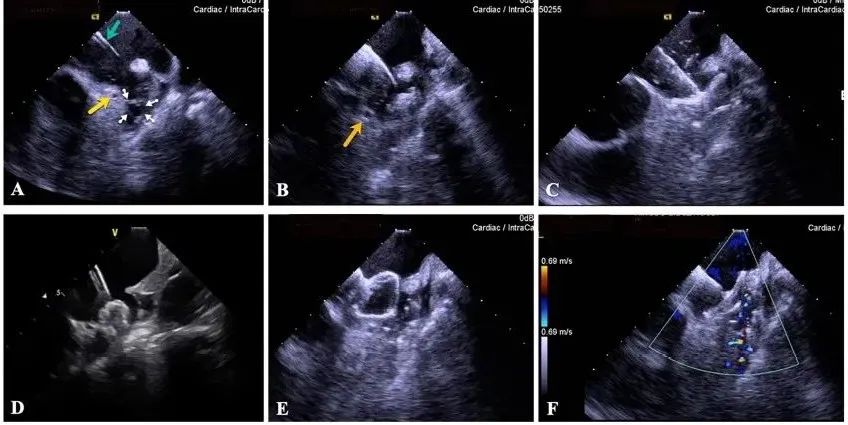

一種與心導管檢查相結合的超聲心動圖診斷新興技術,通過將超聲探頭置于心腔內(nèi)部,發(fā)射并接收超聲信號,來精確獲取心臟解剖結構、心臟血流動力學等信息的實時成像。與其他影像技術相比,ICE技術具有操作簡單、無輻射、安全性高、手術效率高、實用等優(yōu)勢,ICE在很大程度上有望取代經(jīng)食道超聲心動圖(TEE),成為電生理和結構性心臟病領域的理想成像方式。

目前ICE技術已被應用于左心耳封堵、房顫射頻消融、二尖瓣成形、房間隔缺損封堵等多種心臟介入手術,應用場景主要圍繞心臟電生理、結構性心臟病等領域,目前以電生理應用為主。數(shù)據(jù)顯示,我國結構性心臟病介入器械市場規(guī)模已從2017年的4億元增長至2021年的20億元,年復合增長率達48.3%;預計到2025年,該市場規(guī)模將達到104億元,可以預見ICE市場規(guī)模也將同步高速增長,未來市場發(fā)展空間廣闊。

心腔內(nèi)超聲(ICE)技術壁壘極高,國內(nèi)主要廠商核心部件仍舊為進口,集成了超聲和圖像處理最前端技術,包括超聲探頭、線纜、軟件成像算法等,是當前內(nèi)窺超聲方向最具挑戰(zhàn)的領域。ICE的應用經(jīng)歷了2D平面成像、3D三維立體成像、以及4D的實時三維立體成像階段。